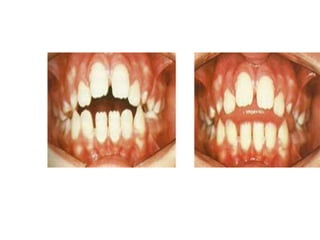

Efectos bucales de la deglución

atípica:

• Mordida abierta anterior simétrica.

• Protrusión de dientes anterosuperiores y aparición

de diastemas.

• Labio superior hipotónico e inferior hipertónico

• Hipertonicidad de la borla de mentón.

• Hiperactividad de los músculos de la masticación.

• Inhibición del crecimiento vertical del proceso

alveolar.

• Incompetencia labial.

• Problemas fonéticos.

• Mordida abierta anterior.

deglución normal

deglución atípica